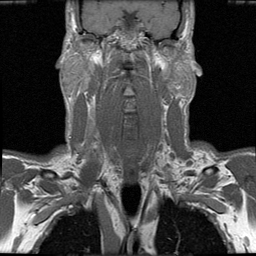

To simulate various input noise levels, several values for have been selected in the range . The set of high-quality magnitude MR test images used is shown in Fig. 6, and may be obtained from http://bigwww.epfl.ch/luisier/MRIdenoising/TestImages.zip.

| Image 1 | Image 2 | Image 3 | Image 4 |

|---|---|---|---|

![]() |